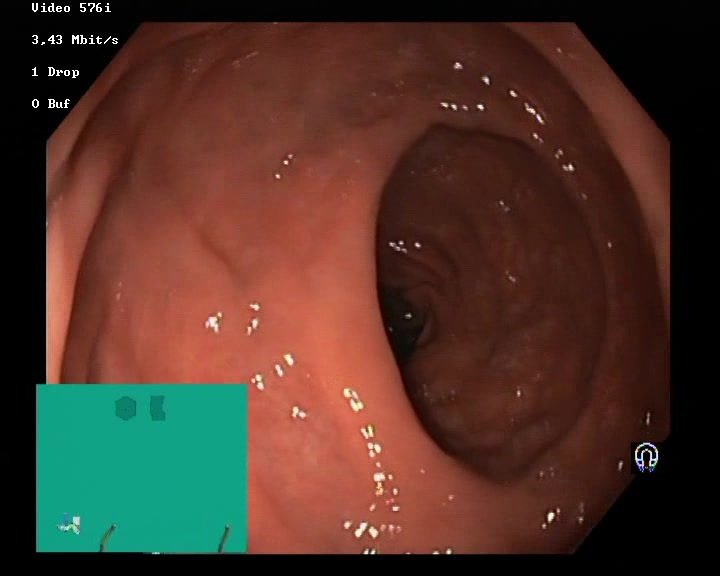

Image of a polyp from a colonoscopy

Gastroscopy and colonoscopy

The gastrointestinal (GI) tract is prone to many different diseases

Doctors use sensor and image data to diagnose

The procedure's success is heavily dependent on the doctor

We can use this data to train machine learning algorithms